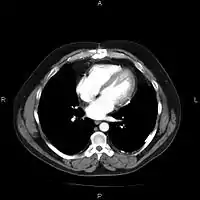

A picture archiving and communication system (PACS) is a medical imaging technology which provides economical storage and convenient access to images from multiple modalities (source machine types).[1] Electronic images and reports are transmitted digitally via PACS; this eliminates the need to manually file, retrieve, or transport film jackets, the folders used to store and protect X-ray film. The universal format for PACS image storage and transfer is DICOM (Digital Imaging and Communications in Medicine). Non-image data, such as scanned documents, may be incorporated using consumer industry standard formats like PDF (Portable Document Format), once encapsulated in DICOM. A PACS consists of four major components: The imaging modalities such as X-ray plain film (PF), computed tomography (CT) and magnetic resonance imaging (MRI), a secured network for the transmission of patient information, workstations for interpreting and reviewing images, and archives for the storage and retrieval of images and reports. Combined with available and emerging web technology, PACS has the ability to deliver timely and efficient access to images, interpretations, and related data. PACS reduces the physical and time barriers associated with traditional film-based image retrieval, distribution, and display.

Most PACS handle images from various medical imaging instruments, including ultrasound (US), magnetic resonance (MR), Nuclear Medicine imaging, positron emission tomography (PET), computed tomography (CT), endoscopy (ES), mammograms (MG), digital radiography (DR), phosphor plate radiography, Histopathology, ophthalmology, etc. Additional types of image formats are always being added. Clinical areas beyond radiology; cardiology, oncology, gastroenterology, and even the laboratory are creating medical images that can be incorporated into PACS. (see DICOM Application areas).